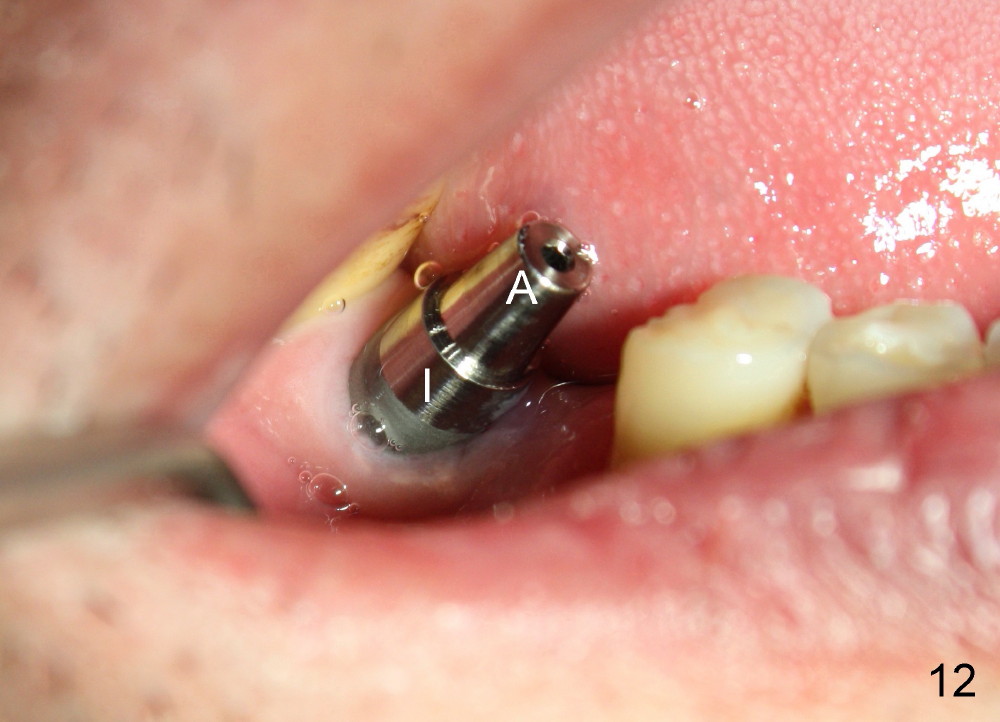

When the perio dressing is removed in office 24 days postop (Fig.9), the rough surface of the implant (R) is exposed buccally. Normally the smooth surface should contact the gingiva (S). Lingually implant/gingiva position is within normal limit (Fig.10). The patient returns for restoration 4 months postop (Fig.11,12). There is bone formation in the mesial socket and new bone appears to have grown toward the implant (Fig.11 <). A straight abutment appears to be in the middle of the edentulous space (Fig.12 A). But it is difficult to seat the crown. Three months post cementation, the patient complains of food impaction mesially (Fig.10 ^), although bone density continues to increase in the mesial socket and there is no mesial coronal thread exposure (*). Retrospectively the implant should be tried to be placed in the septum as much as possible to have a favorable restorative axis (Fig.14). The crown is re-fabricated with larger mesial contact area. It is temporarily cemented because of slightly loose distal contact (Fig.15). A few days later, the patient requests permanent cementation, because although the distal contact is loose, it is easy to remove food. Mesial food impaction is less likely, but it is more difficult to be removed.